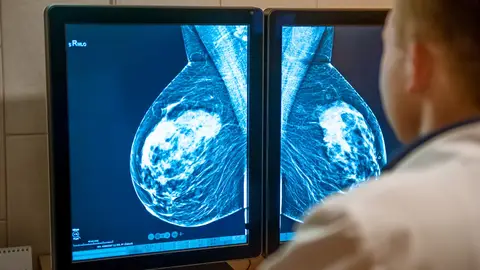

A favor, diagnósticos cada vez más rápidos y certeros, gracias a la IA. "Lo que antes se tardaba varias semanas en saber, ahora con este software de IA, tenemos el resultado en apenas treinta segundos"